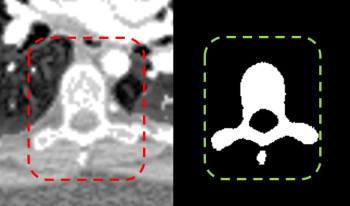

Spinal CT image segmentation is actively researched in the field of medical image processing. However, due to factors such as high variability among spinal CT slices and image artifacts, and so on, automatic and accurate spinal CT segmentation tasks are extremely challenging. To address these issues, we propose a cascaded U-shaped framework that combines multi-scale features and attention mechanisms (MA-WNet) for the automatic segmentation of spinal CT images. Specifically, our framework combines two U-shaped networks to achieve coarse and fine segmentation separately for spinal CT images. Within each U-shaped network, we add multi-scale feature extraction modules during both the encoding and decoding phases to address variations in spine shape across different slices. Additionally, various attention mechanisms are embedded to mitigate the effects of image artifacts and irrelevant information on segmentation outcomes. Experimental results show that our proposed method achieves average segmentation Dice similarity coefficients of 94.53% and 91.38% on the CSI 2014 and VerSe 2020 datasets, respectively, indicating highly accurate segmentation performance, which is valuable for potential clinical applications.